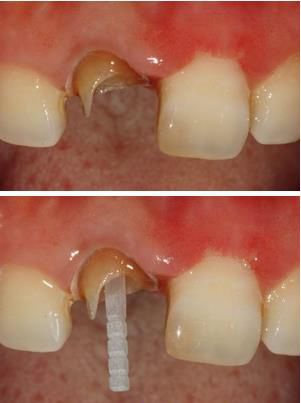

在操作的過程中要注意無菌操作,保證纖維樁的無菌狀態(tài)。推薦將樹脂核堆好之后再截?cái)嗬w維樁,而不是截?cái)嗪笤僬辰印H缦聢D: